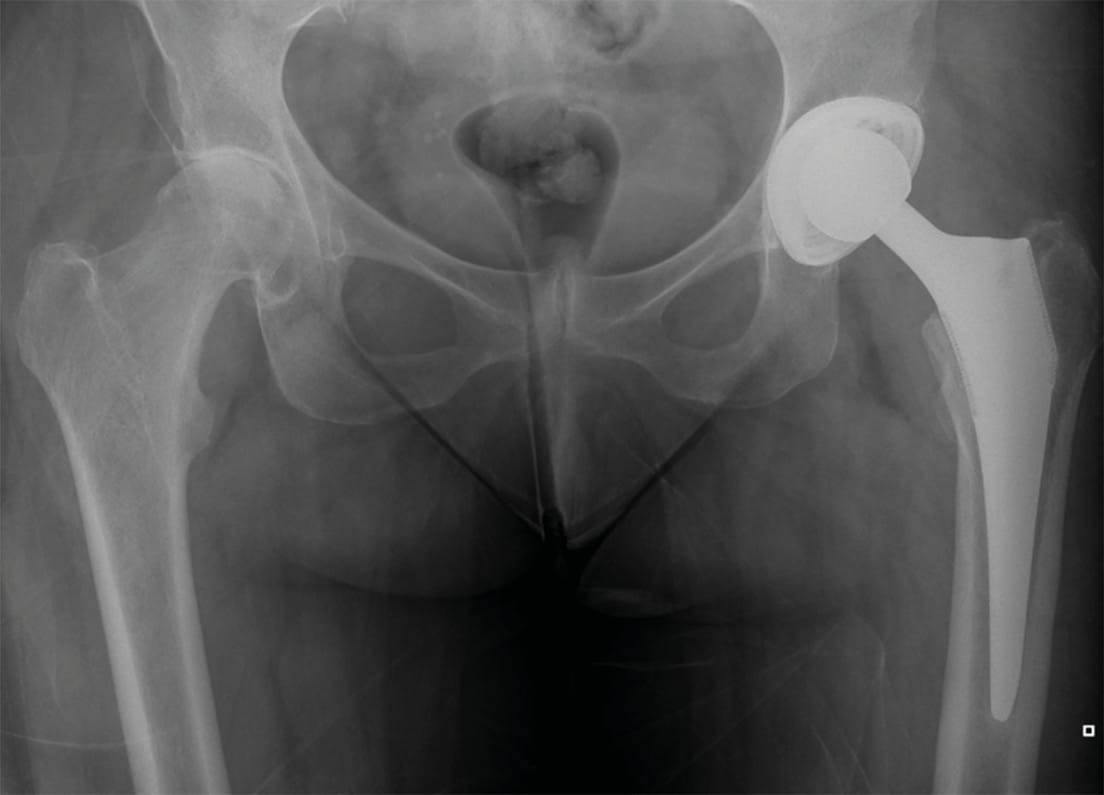

An empirical antibiotic therapy with Vancomycin and Ceftazidime was started. After one week (day 8) of culture in enriched media, Granulicatella adiacens was recovered and, according to the antibiogram, ATB was adapted to Ceftriaxone 1g/12 hours + Gentamicin 80 mg/ 8 hours for four weeks following by 8 weeks of minocycline orally. Sensitivity to Vancomycin was also reported. As additional data, the samples from the arthroscopy were negative. In addition, given the association of this germ with bacterial endocarditis, although she was asymptomatic, an echocardiogram was performed, and endocarditis was concomitantly diagnosed. Two weeks after treatment, she started again with pain in the right hip, so xray, laboratory and hip MRI were repeated. Xray showed chondrolysis with loss of the joint space. The laboratory values were similar to those of the initial diagnosis, while MRI showed hyperintensity in the femoral head in the STIR sequence, interpreted as subchondral necrosis secondary to septic arthritis. (Figures 3-4).